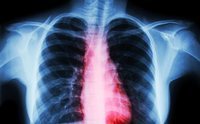

Un infarto pulmonar ocurre cuando una sección del tejido pulmonar muere porque su suministro de sangre se ha bloqueado. Si bien varias afecciones médicas pueden causar un infarto pulmonar, la causa más común es la embolia pulmonar. Dependiendo de su tamaño y ubicación, los síntomas de un infarto pulmonar pueden ser desde muy leves hasta extremadamente severos. Sin embargo, independientemente de sus síntomas, un infarto pulmonar siempre indica la presencia de un problema médico subyacente grave y siempre requiere una evaluación y un tratamiento agresivo.

La causa más común de infarto pulmonar es un émbolo pulmonar. Ahora se estima que hasta el 30% de los émbolos pulmonares producen infartos pulmonares. Otras afecciones médicas también pueden causar un infarto pulmonar al producir oclusión de parte de la circulación pulmonar. Estos incluyen cáncer, enfermedades autoinmunes como lupus, diversas infecciones, enfermedad de células falciformes, enfermedades pulmonares infiltrantes como amiloidosis o embolización de aire u otros materiales de un catéter intravenoso. Los drogadictos por vía intravenosa son particularmente propensos a desarrollar infartos pulmonares.

Cualquiera que sea la causa, los infartos pulmonares muy grandes son relativamente infrecuentes, ya que el tejido pulmonar tiene tres fuentes potenciales de oxígeno : la arteria pulmonar, la arteria bronquial (arterias que suministran al árbol bronquial) y los alvéolos (los sacos de aire dentro de los pulmones) . Esto significa que los infartos pulmonares potencialmente mortales se observan con mayor frecuencia en personas que tienen problemas médicos subyacentes significativos, como la enfermedad pulmonar obstructiva crónica (EPOC) o una insuficiencia cardíaca crónica . En particular, los fumadores también tienen un riesgo mucho mayor de infartos pulmonares.